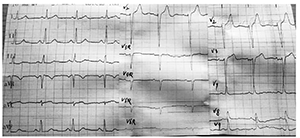

患者 男,43岁,因"反复胸前区疼痛约10 h,加重约3 h"入院。患者2014年2月5日早晨8: 00左右无明显诱因突然出现胸前区、上腹部阵发性疼痛,疼痛位置不固定,向背部放射,伴有胸闷,症状数分钟后能自行缓解,但症状反复发作,当日13: 00来我院诊治,14: 05查丙氨酸氨基转移酶(ALT) 25 U/L(正常值9~ 52 U/L)、天冬氨酸氨基转移酶(AST) 33 U/L(正常值15~ 46 U/L )、乳酸脱氢酶(LDH) 442 U/L(正常值313~ 618 U/L)、肌酸激酶(CK) 71 U/L(正常值30~ 170 U/L )、肌酸激酶同工酶(CK-MB) 20 U/L(正常值0~ 16 U/L)。患者14: 27胸痛间歇期查十二导联心电图示下侧壁导联ST段改变(图1),后患者疼痛有所好转,拟诊腹痛待查,不排除冠心病、心绞痛,给予麝香保心丸后患者离院。15: 00左右患者疼痛加重,剑突下疼痛明显,症状持续不缓解,阵发性加剧,伴有恶心、呕吐、出汗,无晕厥、心悸、呼吸困难,收入院进一步诊治。患者平素吸烟,每天约吸1包烟,否认高血压、糖尿病病史。查体:血压154/109 mmHg (1 mmHg= 0.133 kPa),两肺未闻及干、湿性啰音,心率92次/min,律齐,无杂音,腹平软,上腹部轻压痛,无反跳痛,未触及包块,肝脾肋缘下未触及,Murphy征阴性,肝肾区无叩击痛,双下肢无水肿。胸部X线片无异常。18: 25十二导联心电图无异常(图2)。18: 26查ALT 28 U/L、AST 19 U/L、LDH 433 U/L、CK 83 U/L、CK-MB 16 U/L,血糖、肾功能、血淀粉酶、凝血功能无异常。给予吸氧、严密监护、抗血小板聚集、扩张冠状动脉等处理。胸部、腹部增强CT未见胸腹部异常情况,无主动脉夹层形成。患者症状缓解不明显。22: 30查ALT 27 U/L、AST 36 U/L、LDH 431 U/L、CK 289 U/L、CK-MB 58 U/L,肌钙蛋白T 253 ng/L,血淀粉酶正常。次日0: 10十八导联心电图正常(图3, 图4)。诊断为冠心病、急性心肌梗死、心功能Killip 1级,行冠状动脉造影检查:左前降支近中段狭窄30%,对角支无狭窄;左主干无狭窄;右冠状动脉无狭窄,左回旋支近段完全闭塞;各血管间未见明显的侧支循环(图5)。手术中发现左回旋支近段严重固定狭窄并急性闭塞,予回旋支植入2枚药物支架。数天后患者病情好转出院。